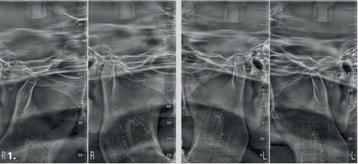

Temporomandibular joints: right and left, with open or closed mouth, and in latero-lateral and posteroanterior projections with multi-angle projection